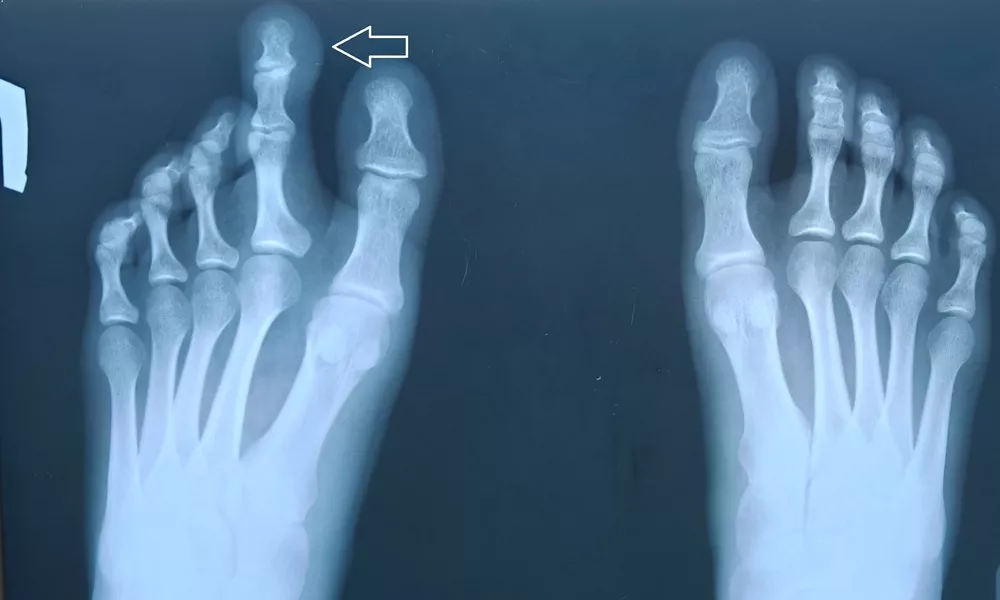

Как рассказали в пресс-службе центра, за помощью с такой проблемой обратилась 17-летняя девушка с сильным увеличением второго пальца на левой ноге. Помимо очевидного косметического дефекта она также не могла найти подходящую ей обувь. Травматолог-ортопед принял решение о необходимости хирургического вмешательства в этой ситуации.

В ходе операции бригада врачей выполнила реконструкцию пальца: укоротили костную фалангу и зафиксировали ее специальной спицей, а также удалили лишние мягкие ткани. Весь процесс прошел успешно и медикам удалось сформировать эстетически правильный и подвижный палец. Пациентка выразила огромную благодарность специалистам за возможность вести комфортную жизнь.